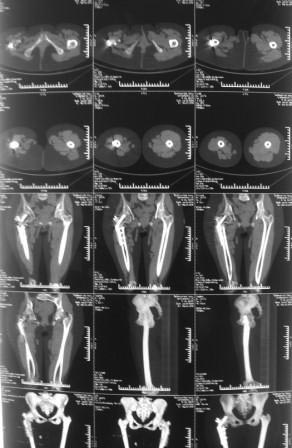

На Р-грамме, похоже, клинок пластины сломан, сращения нет.

В плане, учитывая возраст, эндопротезирование пока рано, может,

попробовать БИОС с рассверливанием , т.к мешающей контрактуры  нет, и

пусть походит, поживет, потом эндопротез.